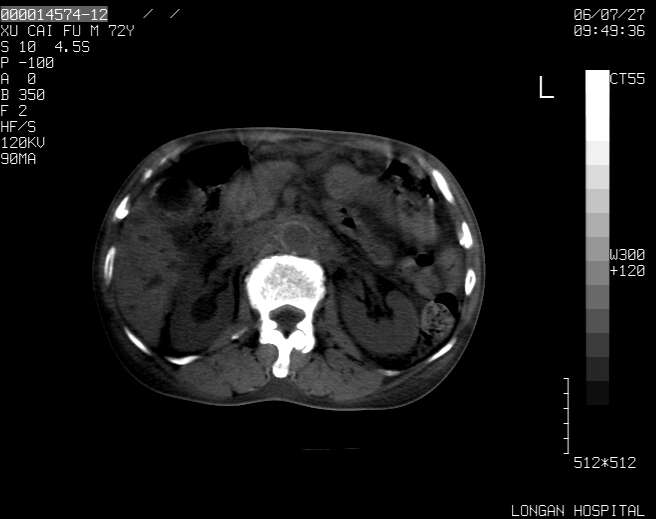

以下是引用winter在2006-7-30 20:14:00的发言:[br]1、考虑胆囊癌伴胆道侵犯并高位胆道梗阻、肝内多发转移、腹膜后淋巴结转移。[br]2、右肾轻度积水。[br]3、老人家72岁了胰腺头体尾部均较饱满,不过未见密度异常及其他异常征象。[br]4、腹水。

以下是引用jiajie在2006-7-31 7:10:00的发言:[br]考虑肝转移瘤,腹膜后淋巴结增大。[br]胃癌不能除外,建议胃镜检查。